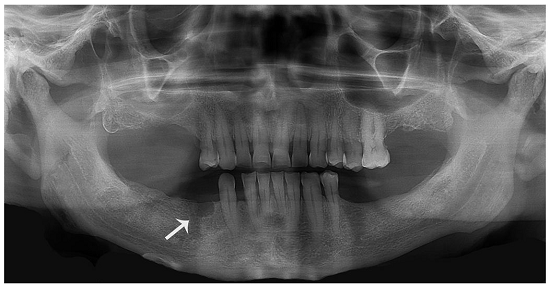

A 66-year-old man was referred to the Stomatology Department complaining of pain in the right mandible over the past year. He reported the exodontia of the first inferior right premolar 1 year ago, which after 4 months, became the site of the current complaint. His medical history included the diagnosis of metastatic prostate adenocarcinoma being treated with goserelin acetate (Zoladex®) over the last 8 years. An SCLC and bone metastasis from the prostate adenocarcinoma were also diagnosed in the past year, and treated with cisplatin (CCDP) and zoledronic acid (Zometa®). Intraoral examination revealed a slightly bluish area located in the overlying mucosa of the edentulous alveolus of the right mandible (first premolar). X-ray revealed a unilocular, oval radiolucency of 0.5 × 0.7 cm with well-defined sclerotic borders (Figure 1).

Radiographically, most cases of metastatic lesions present as osteolytic areas poorly defined with a “moth eaten” appearance.2 The imaging study of our patient was quite different presenting a well-defined margin of the lesion. Consequently, the hypothesis of metastatic SCLC of the mandible was not initially taken into account. Based on the clinical/radiograph findings and previous history of the first premolar’s exodontia, the lesion was initially considered as an odontogenic lesion.